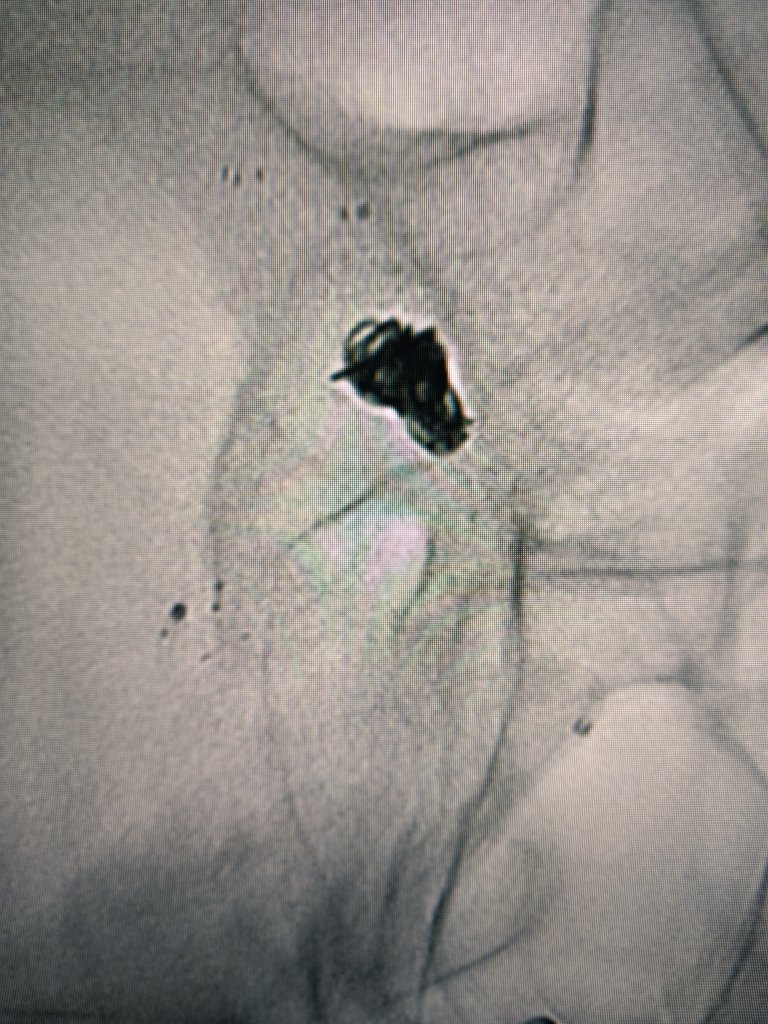

Thrombous at the tip of the iNstroke catheter @CARDIVAGROUP @iVascularGlobal and ICA stenting.

English

Stroke due to left tandem occlusion After crossing the ICA occlusion direct aspiration using nobel 4F iNstroke catheter @iVascularGlobal @CARDIVAGROUP was performed wirh complete recanalization Finally ICA stenting was performed with Wallstent @bostonmedical NIHSS 1 at discharge